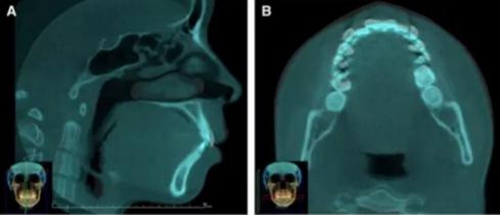

頭側(cè)分析提示為骨性安氏II類(ANB,8.4°;Wits,3.6mm),高角(SN-MP,44.9°),上頜切牙略舌傾(U1-SN,96.2°),下頜切牙略舌傾(IMPA,88。3°)(圖2;表)

治療后頭側(cè)數(shù)據(jù)提示:無明顯骨性變化(上頜SNA82.1°,下頜SNB74.9°),上頜前牙得到內(nèi)收,略舌傾,頦部前后位置無明顯改變,仍未凸面型(圖8,表)。將治療前后圖像重疊后結(jié)果如(圖8及圖9),24月后隨訪結(jié)果見圖10.